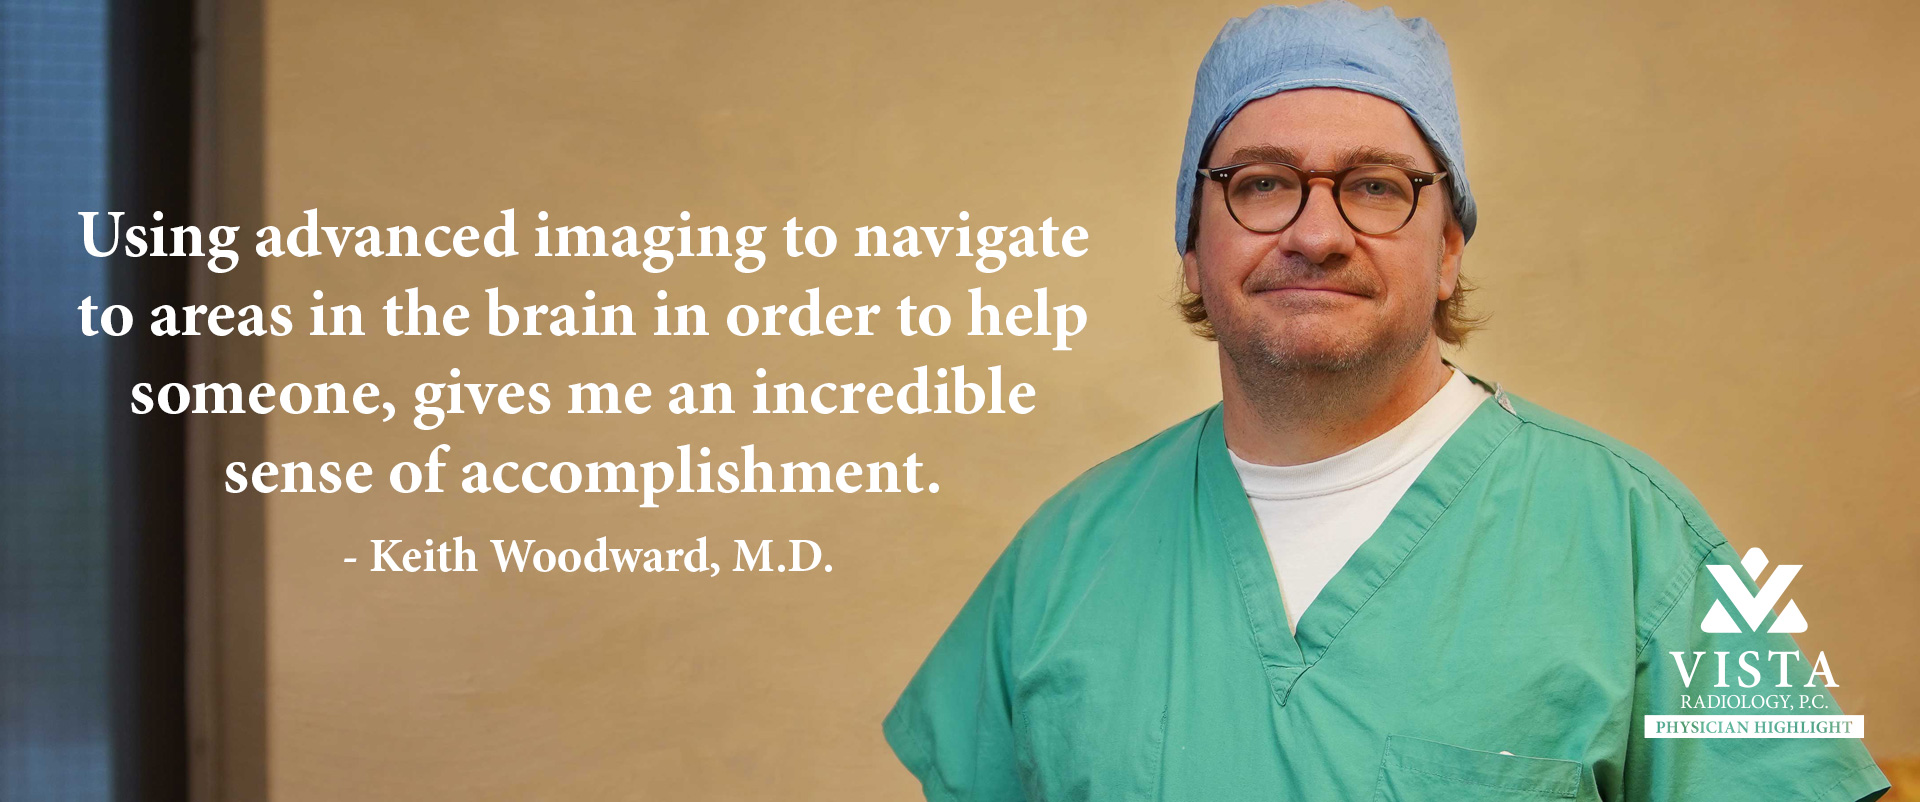

Physicians